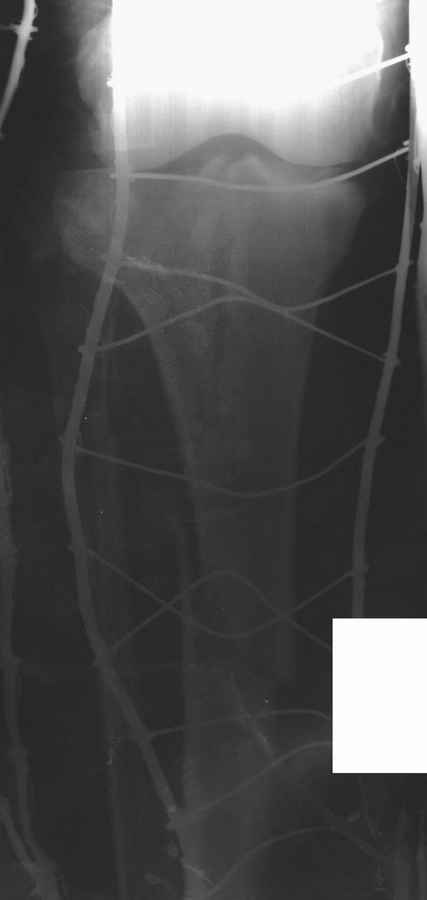

Пациенту сделали КТ - ухитрились сделать на шине Белера (не давал положить прямую ногу) - срезали передний отдел. Планируется на пятницу (24.12) на операцию - синтез длинной мыщелковой LCP-пластиной Synthes :). Отек ближе к слову умеренный (окружность голени +4 см по сравнению со здоровой). КТ и снимок на вытяжении прилагаются.

Трудно поверить, что разрекламированная Ортопедическая школа Восточной Украины позволяет такие странные снимки? На прямом снимке сохранен общий контур плато, но не известна судьба импрессии суставной поверхности. На полубоковой?, оставлен без репозиции задне-медиальный отдел, и навряд ли после такой фиксации можно удовлетвориться результатом.

Представленные снимки не информативны, нужны отдельные качественные снимки коленного сустава и голени без ротации.